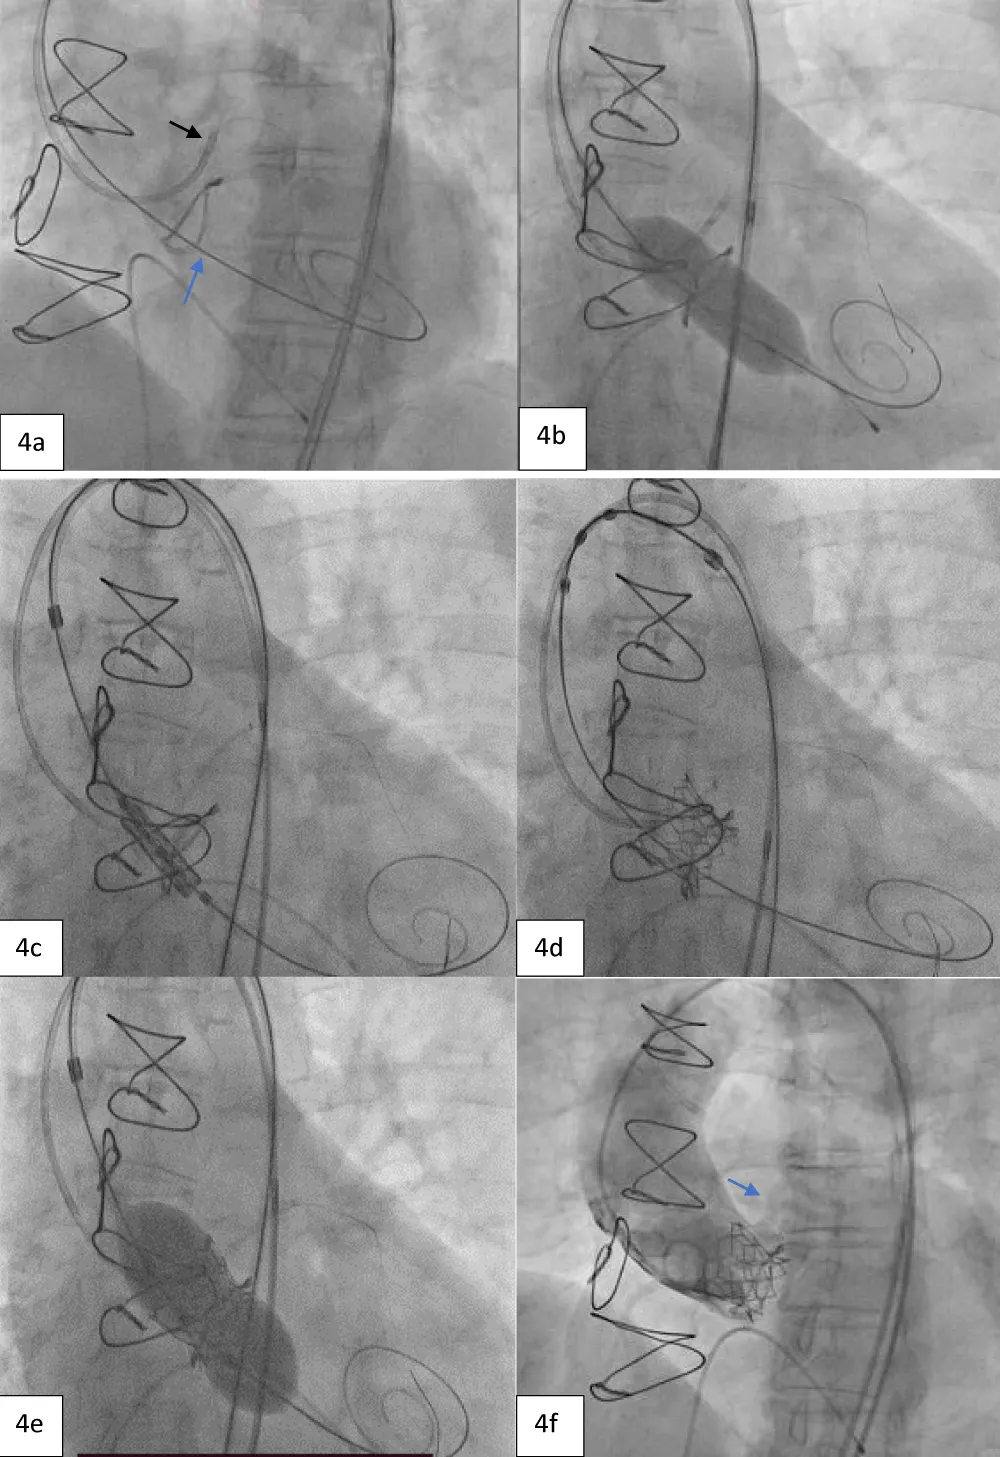

Next, we performed LMCA cannulation using a 6-Fr extra support backup guiding catheter (Medtronic, Minneapolis, USA) followed by placing a 180-cm long, 0.014” Runthrough® straight-tip coronary guidewire (Terumo Medical Corporation, Tokyo, Japan) through the LAD and placing a guide extension catheter in the LMCA (Guidezilla II; Boston Scientific Corporation, Marlborough, Massachusetts, USA) (Figure 4a). This ensured the adequate coronary protection of the LMCA. We proceeded with pre-dilatation for the deployment of the Myval THV using a 20 × 40 mm Mammoth™ balloon (Figure 4b) and deploying the 21.5 mm Myval THV under rapid pacing (Figure 4c,4d). After valve deployment, the patency of LMCA was evaluated by running an aortogram. One post-dilatation was performed using the same balloon by the addition of an extra 2 cm3 inflation volume (Figure 4e) followed by an evaluation of post-valve deployment patency of LMCA on the aortogram (Figure 4F). Upon confirming the final patency of the LMCA, the guide extension catheter from the LMCA and the guidewire from the LAD were gradually retracted. On the postprocedural echocardiogram, the residual peak-to-peak gradient across the left ventricle (LV) and aorta was 9 mmHg (Figure 5), and the mean and peak gradients were 8 mmHg and 8 mmHg. The procedure was completed by wound sealing at the right femoral site with one Proglide® and one Angio-seal® suture (St Jude Medical, St Paul, Minnesota, USA).

Figure 4: Showing protection of left main artery with guide extension catheter and guidewire (black arrow) and Safari stiff wire across the previous prosthetic valve (blue arrow). b. Pre-dilatation with 20x40 mm Mammoth balloon. c. Positioning of 21.5 mm Myval across the previous bioprosthetic valve. d. Deployment of the BE Myval THV with coronary protection in situ. e. Post dilatation performed using the same Mammoth over-the-wire balloon. f. Final aortic root angiogram showing patent LMCA (blue arrow).